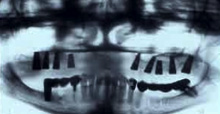

La régénération de l' os maxillaire est, dans la plupart des cas, indispensable à la pose des implants. Lorsqu’une dent est enlevée, l’os restant subi une atrophie. L'atrophie s'accentue avec les années. Cela rend la pose d’un implant difficile ou impossible sans la régénération préalable de l’os.

- Soit un os synthétique est mélangé avec des facteurs de croissance BMP (bone morpho-proteins) de votre sang et est placés dans la mâchoire atrophieés. Cette méthode exclue la chirurgie de la hanche. L’ingénierie génétique des 10 dernières années permet maintenant de régénérer l’os plus vite, en plus grande quantité et qualité et avec une marge parfaite de sûreté par rapport aux autres méthodes.

Notre longue expérience dans la régénération de l’os publiée dans des article et conferances dentaires nous a permis de redonner à nos patients des dents fixes à la place des dentiers. Elle s’applique surtout à la régénération de la mâchoire supérieure et des sinus maxillaires.

Extrait de la conférence du docteur Farsirotu sur le sujet de la régénération osseuse et des sinus maxillaires avec des facteurs de croissance de l’os pour obtenir une dentition fixe sur implants.

Sujet : Les dernières découvertes dans la régénération osseuse et les implants dentaires